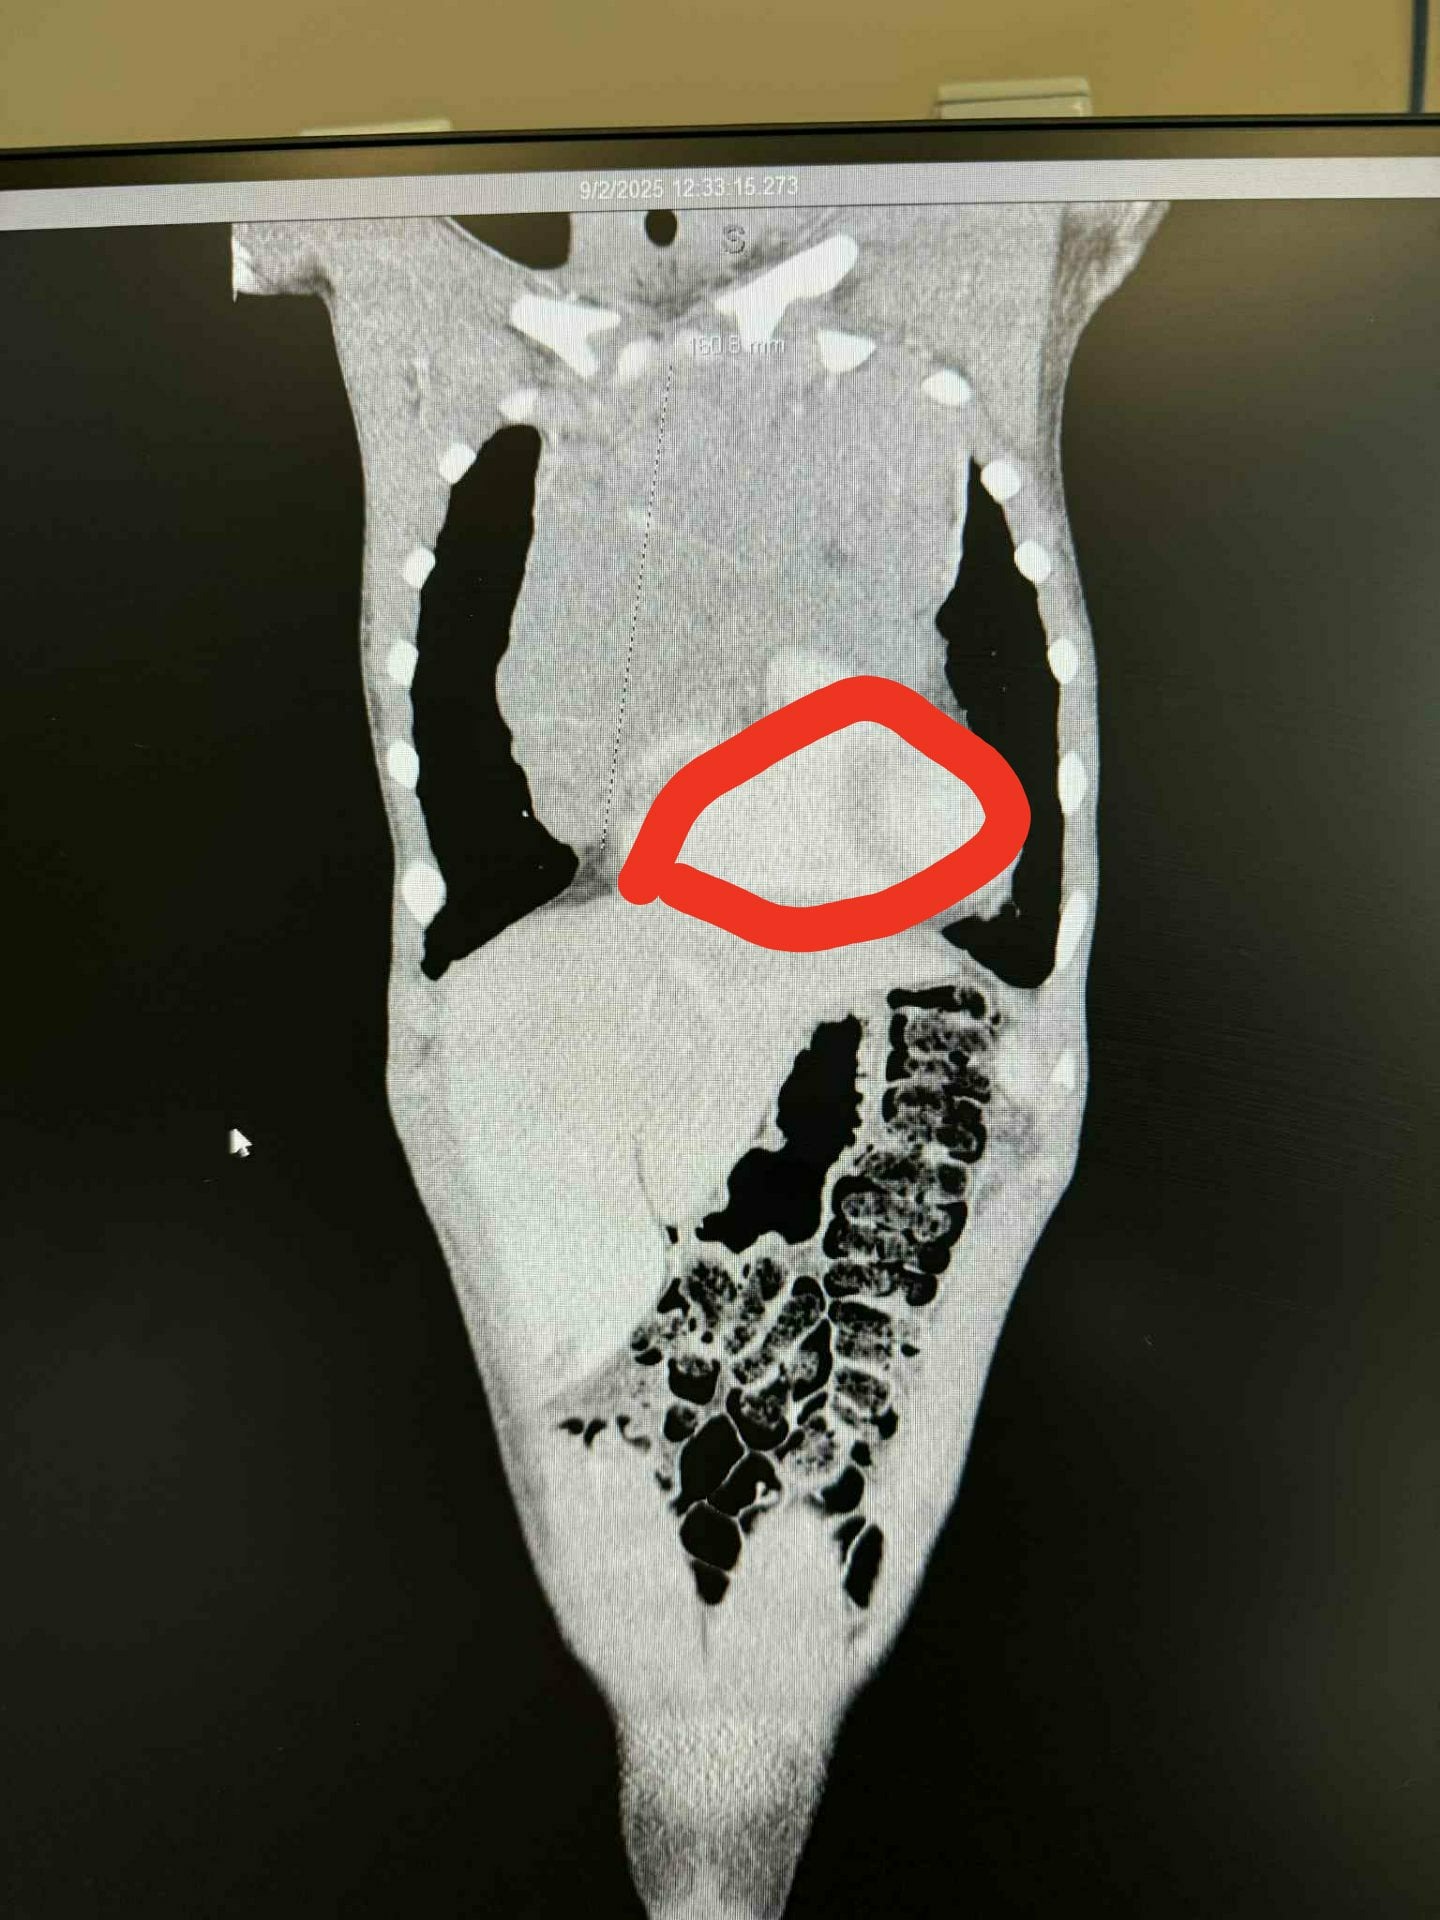

On September 2nd, 2025 Kage was brought to the Emergency Room at Whitman County Hospital complaining of a swollen throat and tongue. When doing a CT Scan on his throat they noticed the top of a large mass in his chest which prompted a second CT Scan of the abdomen. This scan found an extremely large mass pushing on his heart and lungs. He was rushed to Sacred Heart Children's Hospital in Spokane to their oncology center to have further scans and biopsies performed which confirmed Hodgkin's Lymphoma at what was though to be at Stage 2. After spending 7 days in the oncology center and a bout of chemotherapy he was sent home with us. A PET Scan done after the first round of treatment revealed additional tumors in the nodes of his lungs which upgraded the diagnosis to Stage 4.